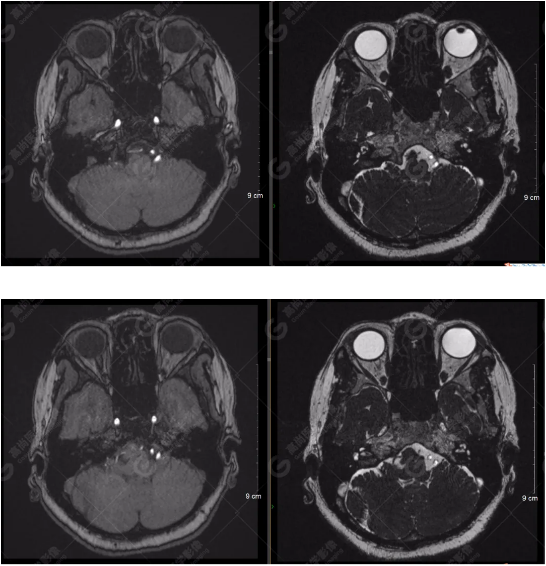

雙側(cè)大腦半球?qū)ΨQ,灰白質(zhì)對(duì)比正常,右側(cè)顳部見一囊狀長T1長T2信號(hào)影,F(xiàn)LAIR序列呈低信號(hào);余腦實(shí)質(zhì)內(nèi)未見局灶性信號(hào)異常。各腦室、腦池大小、形態(tài)均正常,中線結(jié)構(gòu)居中,幕下小腦、腦干無異常。矢狀面示垂體大小形態(tài)正常,未見局灶性信號(hào)異常。

顱腦MRA及ciss序列示腦基底動(dòng)脈環(huán)完整,雙側(cè)頸內(nèi)動(dòng)脈末段、大腦前動(dòng)脈、大腦中動(dòng)脈、大腦后動(dòng)脈及其主要分支顯影良好,管徑及走行正常,無明顯局灶性增粗或變細(xì)。雙側(cè)椎動(dòng)脈末段沿延髓左側(cè)向上走行,左側(cè)面聽神經(jīng)輕度受壓移位,左側(cè)面聽神經(jīng)周圍見細(xì)小血管包繞。右側(cè)面聽神經(jīng)及雙側(cè)三叉神經(jīng)周圍未見異常血管影。

1.雙側(cè)椎動(dòng)脈末段沿延髓左側(cè)向上走行,左側(cè)面聽神經(jīng)輕度受壓移位,左側(cè)面聽神經(jīng)周圍見細(xì)小血管包繞,可符合面聽神經(jīng)壓迫綜合征。

2.右側(cè)顳部蛛網(wǎng)膜囊腫。